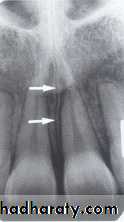

INCISIVE FORAMEN: The incisive foramen is an opening in the bone that is located at the midline of the anterior portion of hard palate. Radiographically the incisive foramen appears as a small ovoid or round radiolucent area located between root of maxillary central incisor.

The superior foramina of the incisive canal are two tiny openings or holes in bone that are located on the floor of the nasal cavity. The superior foramina are the openings of two small canals that extend downward and medially from the floor of the nasal cavity. These two small canals join together to form the incisive canal and share a common exit, the incisive foramen.Appearance. On a maxillary periapical image, the superior foramina appear as two small, round radiolucencies located superior to the apices of the maxillary central incisors

MEDIAN PALATEL SUTURE: The median palatal suture is the immovable joint between two palatine process of maxilla. Radiographically the suture appears as thin radiolucent line between the central incisor, the median palatal suture bounded in both side by dense cortical bone that appear radiopaque.